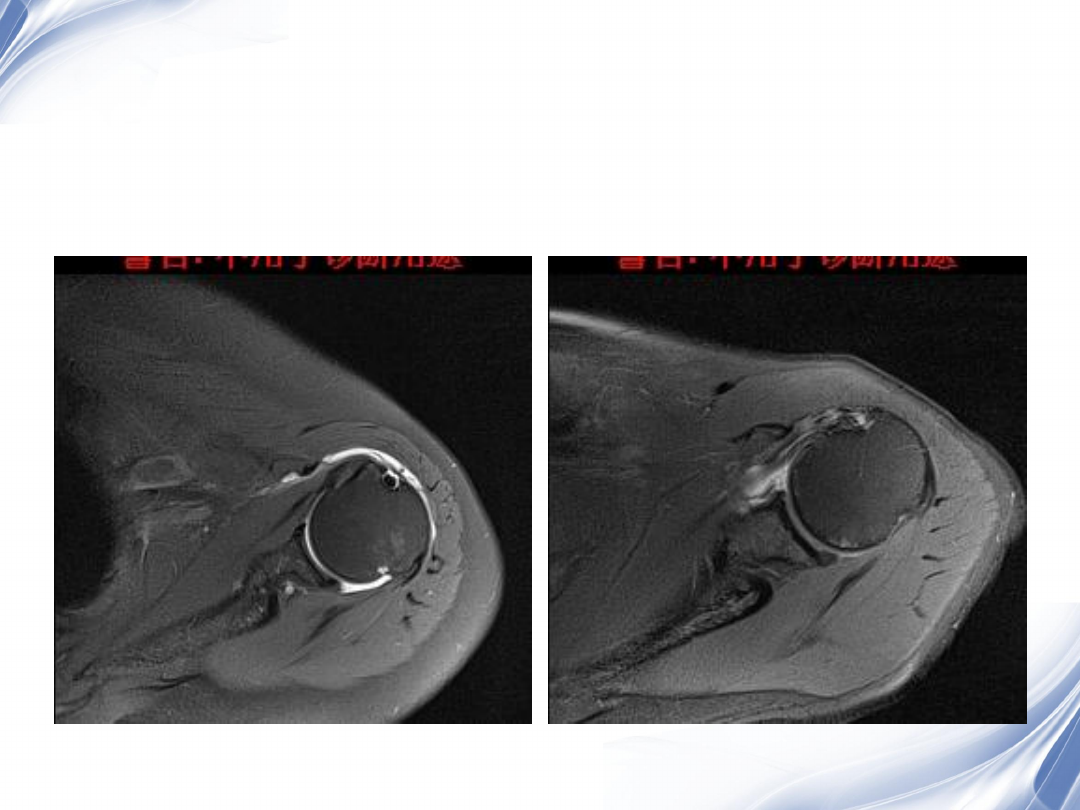

横断位

正常肩胛下肌

肩胛下肌损伤

33

术后

2

37